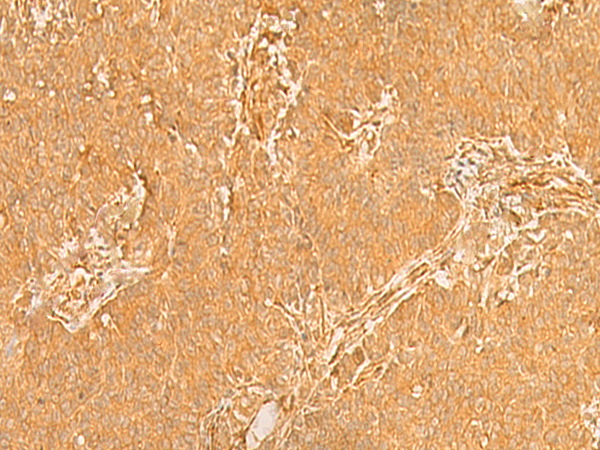

IHC positive control: |

Human breast cancer and Human ovarian cancer |